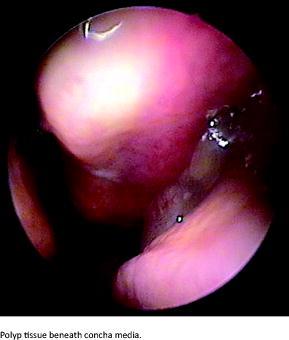

Chronic rhinitis and chronic sinusitis are terms that are often used separately. Since consensus was reached as formulated in the 2007 European Position Paper on Rhinosinusitis and Nasal Polyps (EPOS), the correct term has been chronic rhinosinusitis (CRS) [1, 2]. CRS is defined as inflammation in the nose and paranasal sinus and it is characterized by two or more cardinal symptoms. Either endoscopic signs or computed tomography (CT) changes should be present. A CT was not an option in our study and the diagnosis therefore rests on symptoms and endoscopy. Disease duration is defined as > 12 weeks. If the person was known in advance with a diagnosis of CRS and had been receiving medical treatment, the diagnosis stated was that which appeared in the person’s medical history. The EPOS definition of CRS is shown in Table 1.